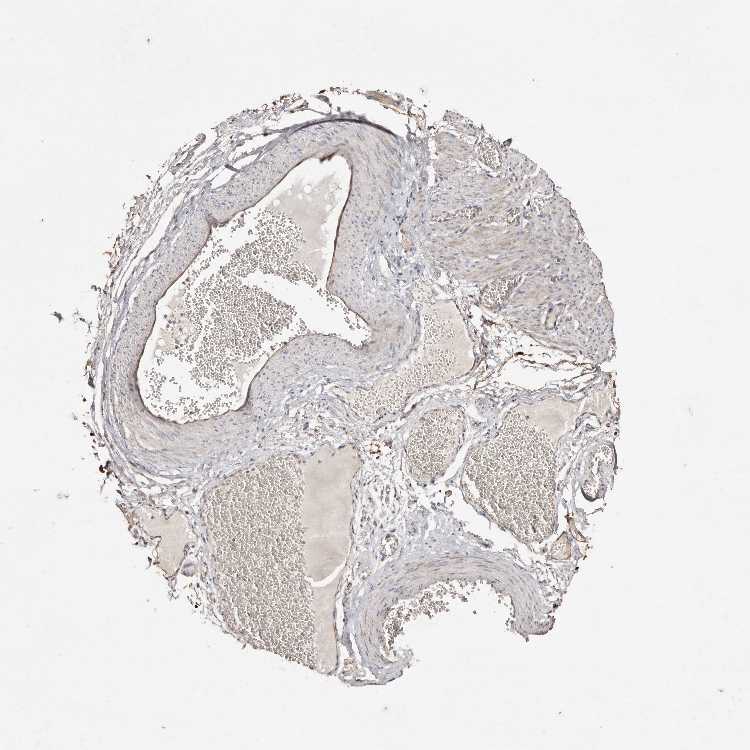

SLC6A20